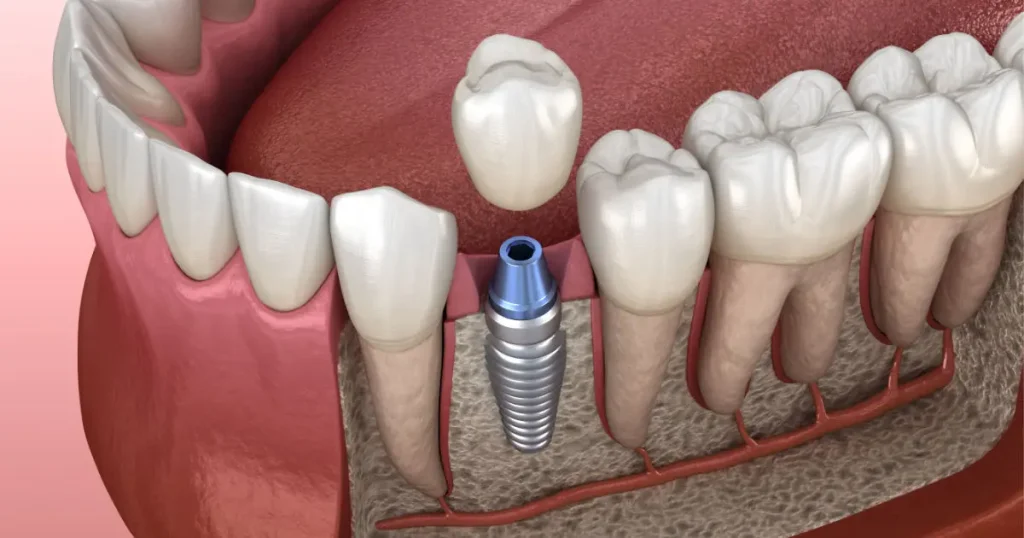

“Los implantes dentales duelen mucho.”

REALIDAD

Gracias a la anestesia moderna y técnicas avanzadas, los implantes son procedimientos seguros, con mínimas molestias y resultados duraderos.